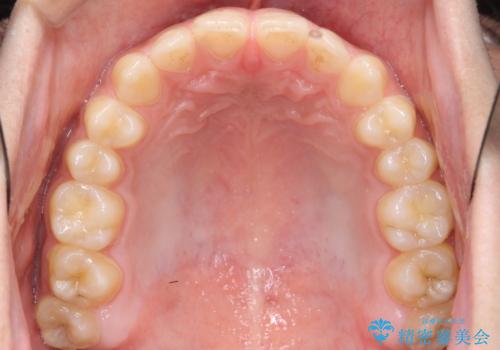

前歯のすきま 受け口 インビザラインで

- 前歯のすき間を気にして来院。

受け口もあり、前歯が端同士であたる、切端咬合となっていました。

下の歯のすき間を閉じて上の歯の内側に入るように位置付けました。

すき間もきれいに閉じ、満足していただきました。

上の前歯は下の歯と直接へりが当たっていた状態(切端咬合)だったため、形がいびつだったのは、わずかにやすりがけをして整えました。

セラミックですき間を閉じようとすると、すきまをうめるために巨大な歯になり、また、下の歯が前に出て強く当たるため、セラミックがかけるおそれがあります。また、下の歯をさけようとすると角度をかえるために歯を極端に削らなければならなくなり、神経をとらなければいけなくなるリスクもあります。

このような歯並びは、セラミックでかぶせるよりは、矯正治療の

適応と言えます。